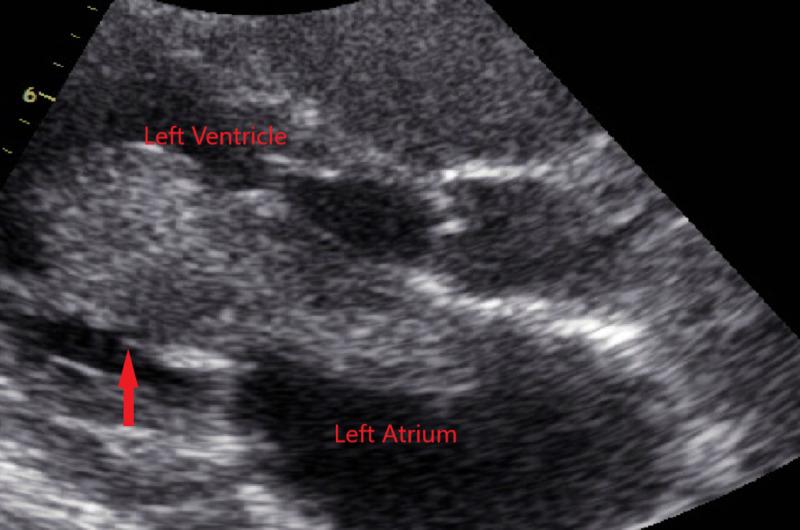

Cardiac myxoma is a benign neoplasm composed of stellate to plump, cytologically bland mesenchymal cells set in a myxoid stroma. Although benign, as they can lead to severe complications, they are often removed surgically. A 39-year-old female presented with a chief complaint of generalized fatigue. Patient had a history of a large 7cm x 2.5cm left atrial myxoma resected at the age of 32 years after she presented with symptoms of dyspnea on exertion. The dyspnea was due to prolapse of the mass through the mitral valve during diastole, leading to functional severe mitral stenosis. The mass was resected with clear margins confirmed on biopsy. On physical examination, heart rate was regular with no murmurs. No signs of congestive heart failure were noted. A 2D echo revealed a mobile structure in the left atrium along with mild mitral regurgitation. Cardiac MRI showed a 21mm x 9mm well defined, pedunculated, mobile mass in the left atrium arising from inter-atrial septum. The mass was hyperintense on T2 weighted images with patchy delayed hyper-enhancement consistent with recurrence of a myxoma. The patient underwent a repeat median sternotomy with the removal of left atrial mass and repair of atrial septum with hemashield patch. The mass was sent for pathological evaluation confirming the diagnosis of recurrent myxoma. On genetic testing, patient tested negative for mutations in PRKAR1A gene (mutated in up to 60%-80% cases with Carney complex), MEN1, RET and sarcoma (TP53) genes. Cardiac myxomas are rare primary benign tumors of the heart with a small recurrence rate. Follow-up studies have rarely reported recurrences after complete resection. However, in our case not only did the patient have the sporadic form of myxoma with recurrence, but it also occurred within three years of the previous resection despite complete removal with clear margins.